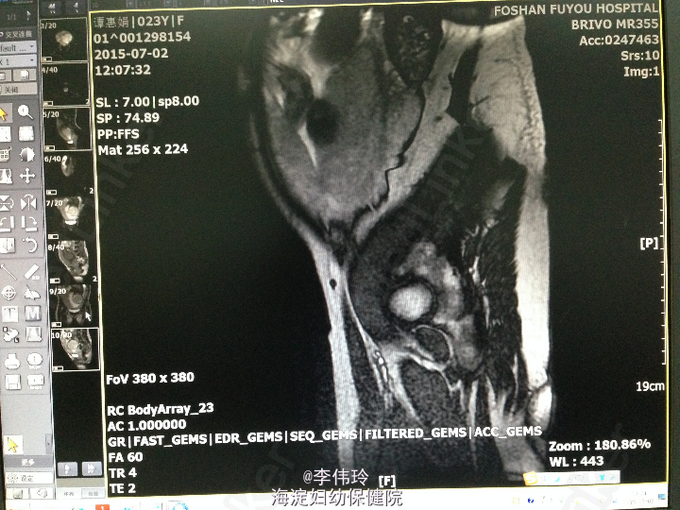

查体:生命体征平稳,心肺未见明显异常。 专科情况:宫高35cm,腹围101cm,胎心音145次/分,扪及无宫缩,宫口未开,胎膜未破。 辅助检查:B超:活单胎,头位,HC相当35+周,FL相当34周,羊水量未见异常。中央型前置胎盘,胎盘成熟度I+度,球拍状胎盘?帆状胎盘?BPS8分,S/D2.1。.MRI:中央型前置胎盘,胎盘信号不均,考虑局部小片状出血,瘢痕子宫改变,未见明显植入征象。母体双肾轻度积水、输尿管中上段扩张。

诊断:G3P1云34+3周LOA单活胎;凶险性中央型前置胎盘;帆状胎盘 处理:行膀胱镜+阿氏切口剖宫产术。术程顺利。

这种情况下一般我们医院都会行MRI了解胎盘植入情况,术前一天会通过产科多普勒定下胎盘位置,研究开口位置,术中用血6u,配血8u去白红细胞。